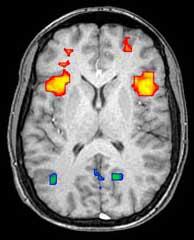

15:14 – Ed: Mike Orth (Ulm, Alemania) estudia la actividad cerebral en personas con la mutación de la enfermedad de Huntington. Los cerebros de los portadores de la mutación de la EH muestran diferentes cantidades de actividad en reposo, e, curiosamente, un aumento de las conexiones entre las áreas. Mike Orth es uno de los científicos a los que entrevistaremos más tarde: los vídeos estarán disponibles poco después.

15:20 – Jeff: Michael Orth, neurólogo de la Universidad de Ulm, estudia los cambios en la «red neuronal por defecto» del cerebro. Estas son las partes del cerebro que están activas cuando estamos «en reposo» o «soñando despiertos» y no pensando en algo específico. Cuando nos centramos en algo específico, estas regiones del cerebro suelen calmarse. En los cerebros de los portadores de la mutación de la EH, esta calma es incompleta, por razones que aún no están claras. Científicos como Michael Orth utilizan una técnica llamada «resonancia magnética funcional», o RMf, para estudiar qué partes del cerebro están activas en un momento dado.

15:27 – Ed: Nellie Georgiou-Karistianis (Australia) también está hablando de la actividad cerebral. La Dra. G-K utiliza pruebas de pensamiento en un escáner de resonancia magnética funcional para desafiar y sondear la función cerebral en los portadores de la mutación de la enfermedad de Huntington. Está utilizando la RMf repetidamente a lo largo del tiempo, podemos ver qué cambios se producen en la EH y qué podemos medir, y tratar de salvar con los tratamientos.